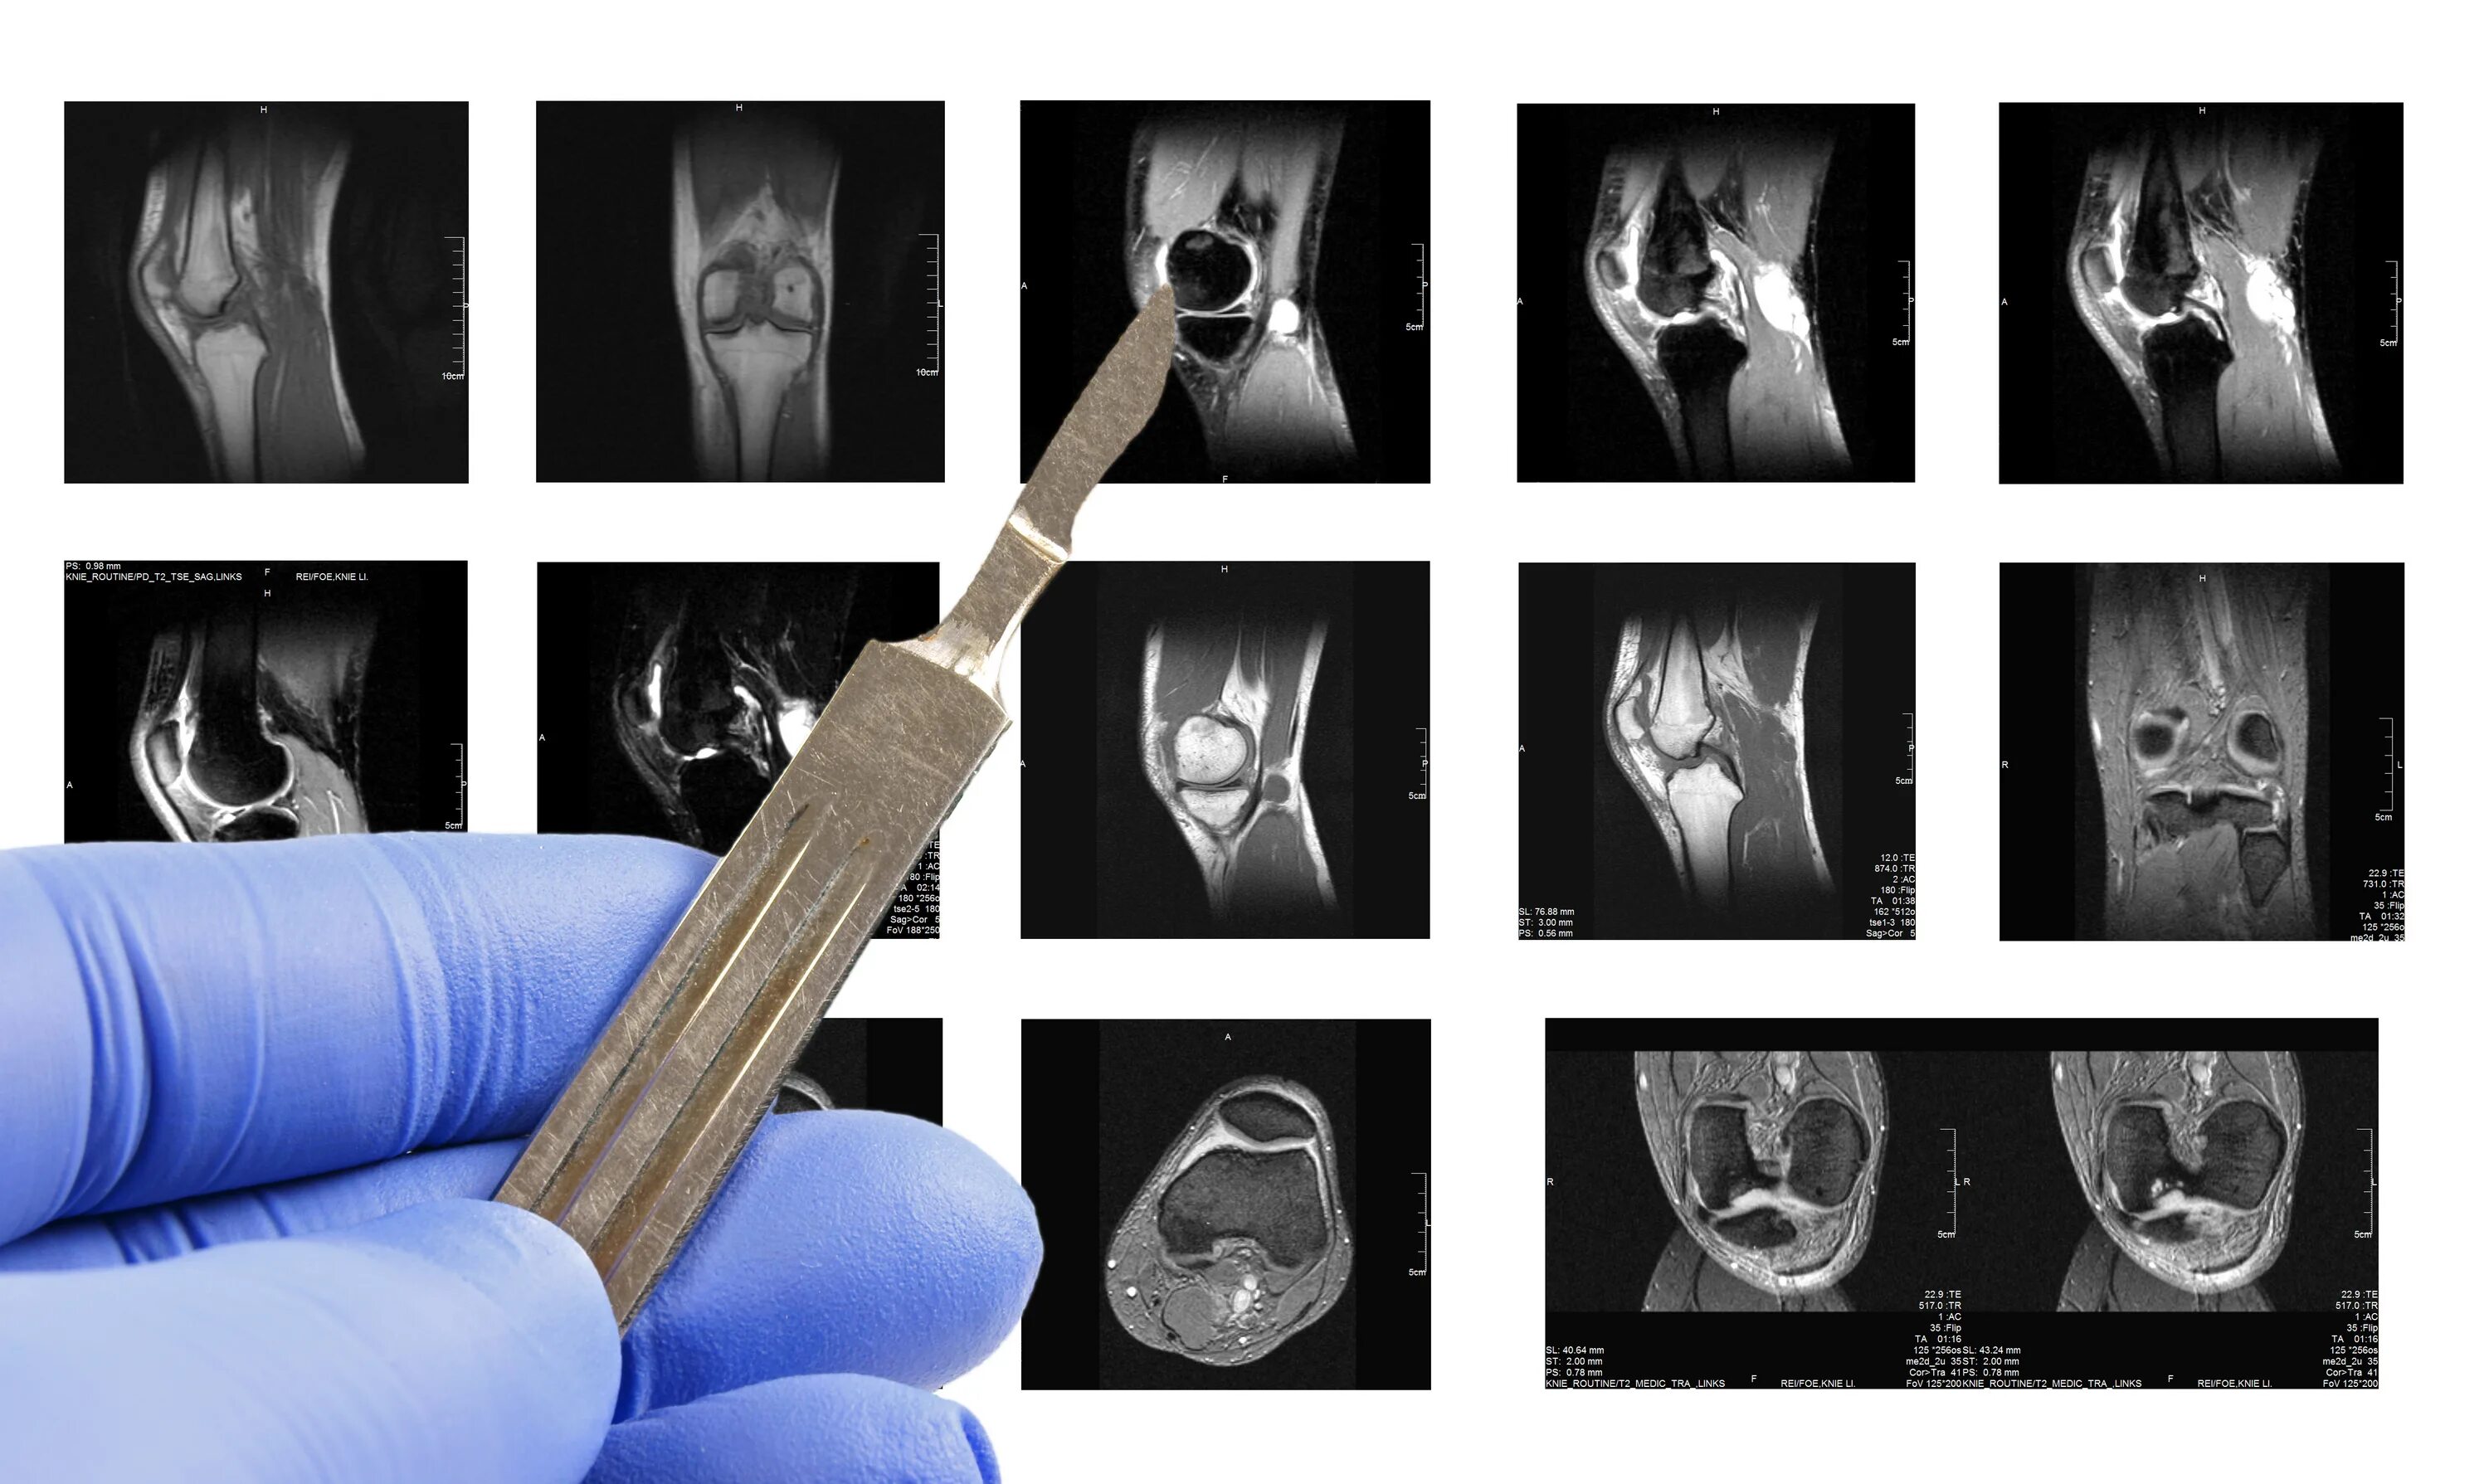

Гонартроз мрт